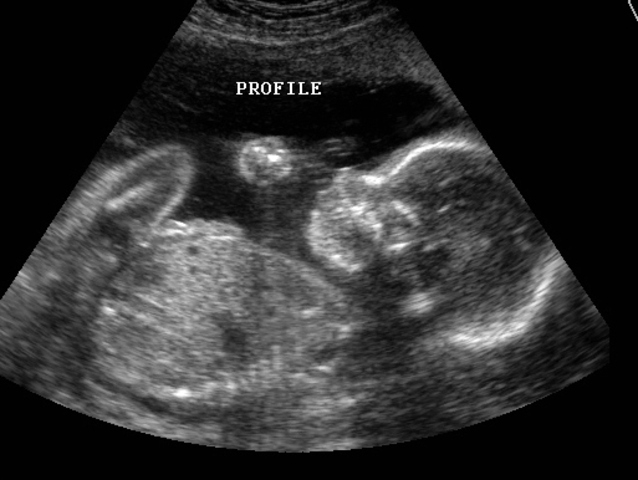

• Gender of the Baby

Gender of the Baby

The gender of the baby with the newer technology can be found around this time (approxomately 12-14 weeks). The sex is usually found with an ultrasound machine. An ultrasound uses different vibrations or sound to capture what the baby looks like.